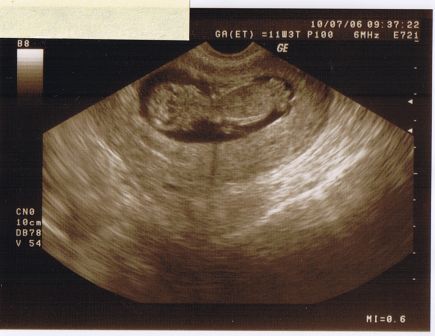

Meine Mama war heute beim Ultraschall. Hihi, wie die gestaunt hat. 5 cm bin ich schon groß - vom Kopf bis zum Steiß. Sie konnte es nicht fassen als sie meinen winzigen Brustkorb gesehen hat, der schwarze Punkt, der meine Blase ist. Die Wirbelsäule sitzt auch richtig. Von oben haben sie in mein Gehirn geguckt. 2 Hälften vorhanden - da grinste Mama, weil die wohl nicht von Papa sind. Als sie meine Ohren sah, fragte sie nur panisch, ob das Segelohren seien. Weil irgendwas muss ich ja vom Papa haben - lach. Meine Ärmchen und Beinchen sind am Wachsen, aber noch sooo klein. Zum Abstoßen reichen sie aber. Das mach ich nämlich am liebsten. Als Mama sah, wie ich im Planschbecken rumschwamm, musste sie so doll lachen, dass ich gleich mithopste. Den ganzen Tag über hat Mama in sich hinein gestrahlt und jedem ganz glücklich erzählt, wie aktiv ich schon bin. Aktiver als sie auf jeden Fall - ätsch. Den nächsten Termin hat sie erst in 5 Wochen. So lange hält sie das bestimmt kaum aus. Und wenn sie mich dann nicht sehen kann, weil kein Ultraschall fällig ist - ooojeee, muss ich mich wohl doch langsam mal bemerkbar machen.